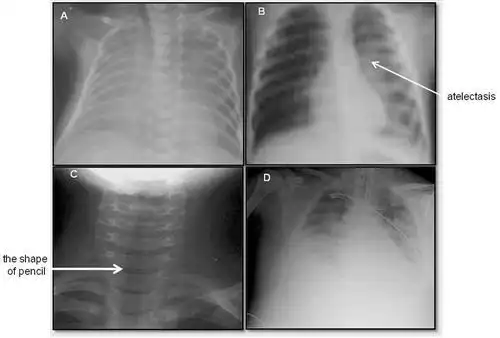

这几组患儿胸片是肺炎还是正常影像规培医师懵了

柳河县医院儿科近两年诊治125例大叶性肺炎总结

小儿呼吸道合胞病毒肺炎

新生儿肺部常见疾病的x线诊断2 新生儿感染性肺炎 男,3天.